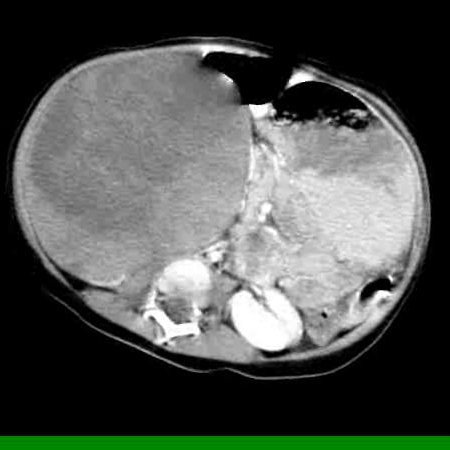

Рисунок 2. КТ: опухоль при поступлении. Клинически: при пальпации опухоль в проекции правой почки до 12 см в диаметре. Общеклинические исследования в пределах возрастной нормы. При КТ органов брюшной и грудной полости: КТ-картина объемного образования правой почки без признаков интрапульмональных метастазов (см. рис. 2). УЗИ брюшной полости: в проекции правой почки солидно-кистозное образование 101ґ114ґ99 мм, объемом 500 мл, васкуляризация активная, интактная часть почки 57ґ12ґ40 мм. Объемное образование правой почки — опухоль Вильмса. Предварительный диагноз: опухоль Вильмса правой почки, 2-я стадия.

Рисунок 3. Контрольная КТ: опухоль после предоперационной химиотерапии. Ребенку проведена предоперационная химиотерапия. На 5-й неделе лечения КТ-контроль показал уменьшение опухоли в размерах до 90ґ80ґ100 мм (см. рис. 3).